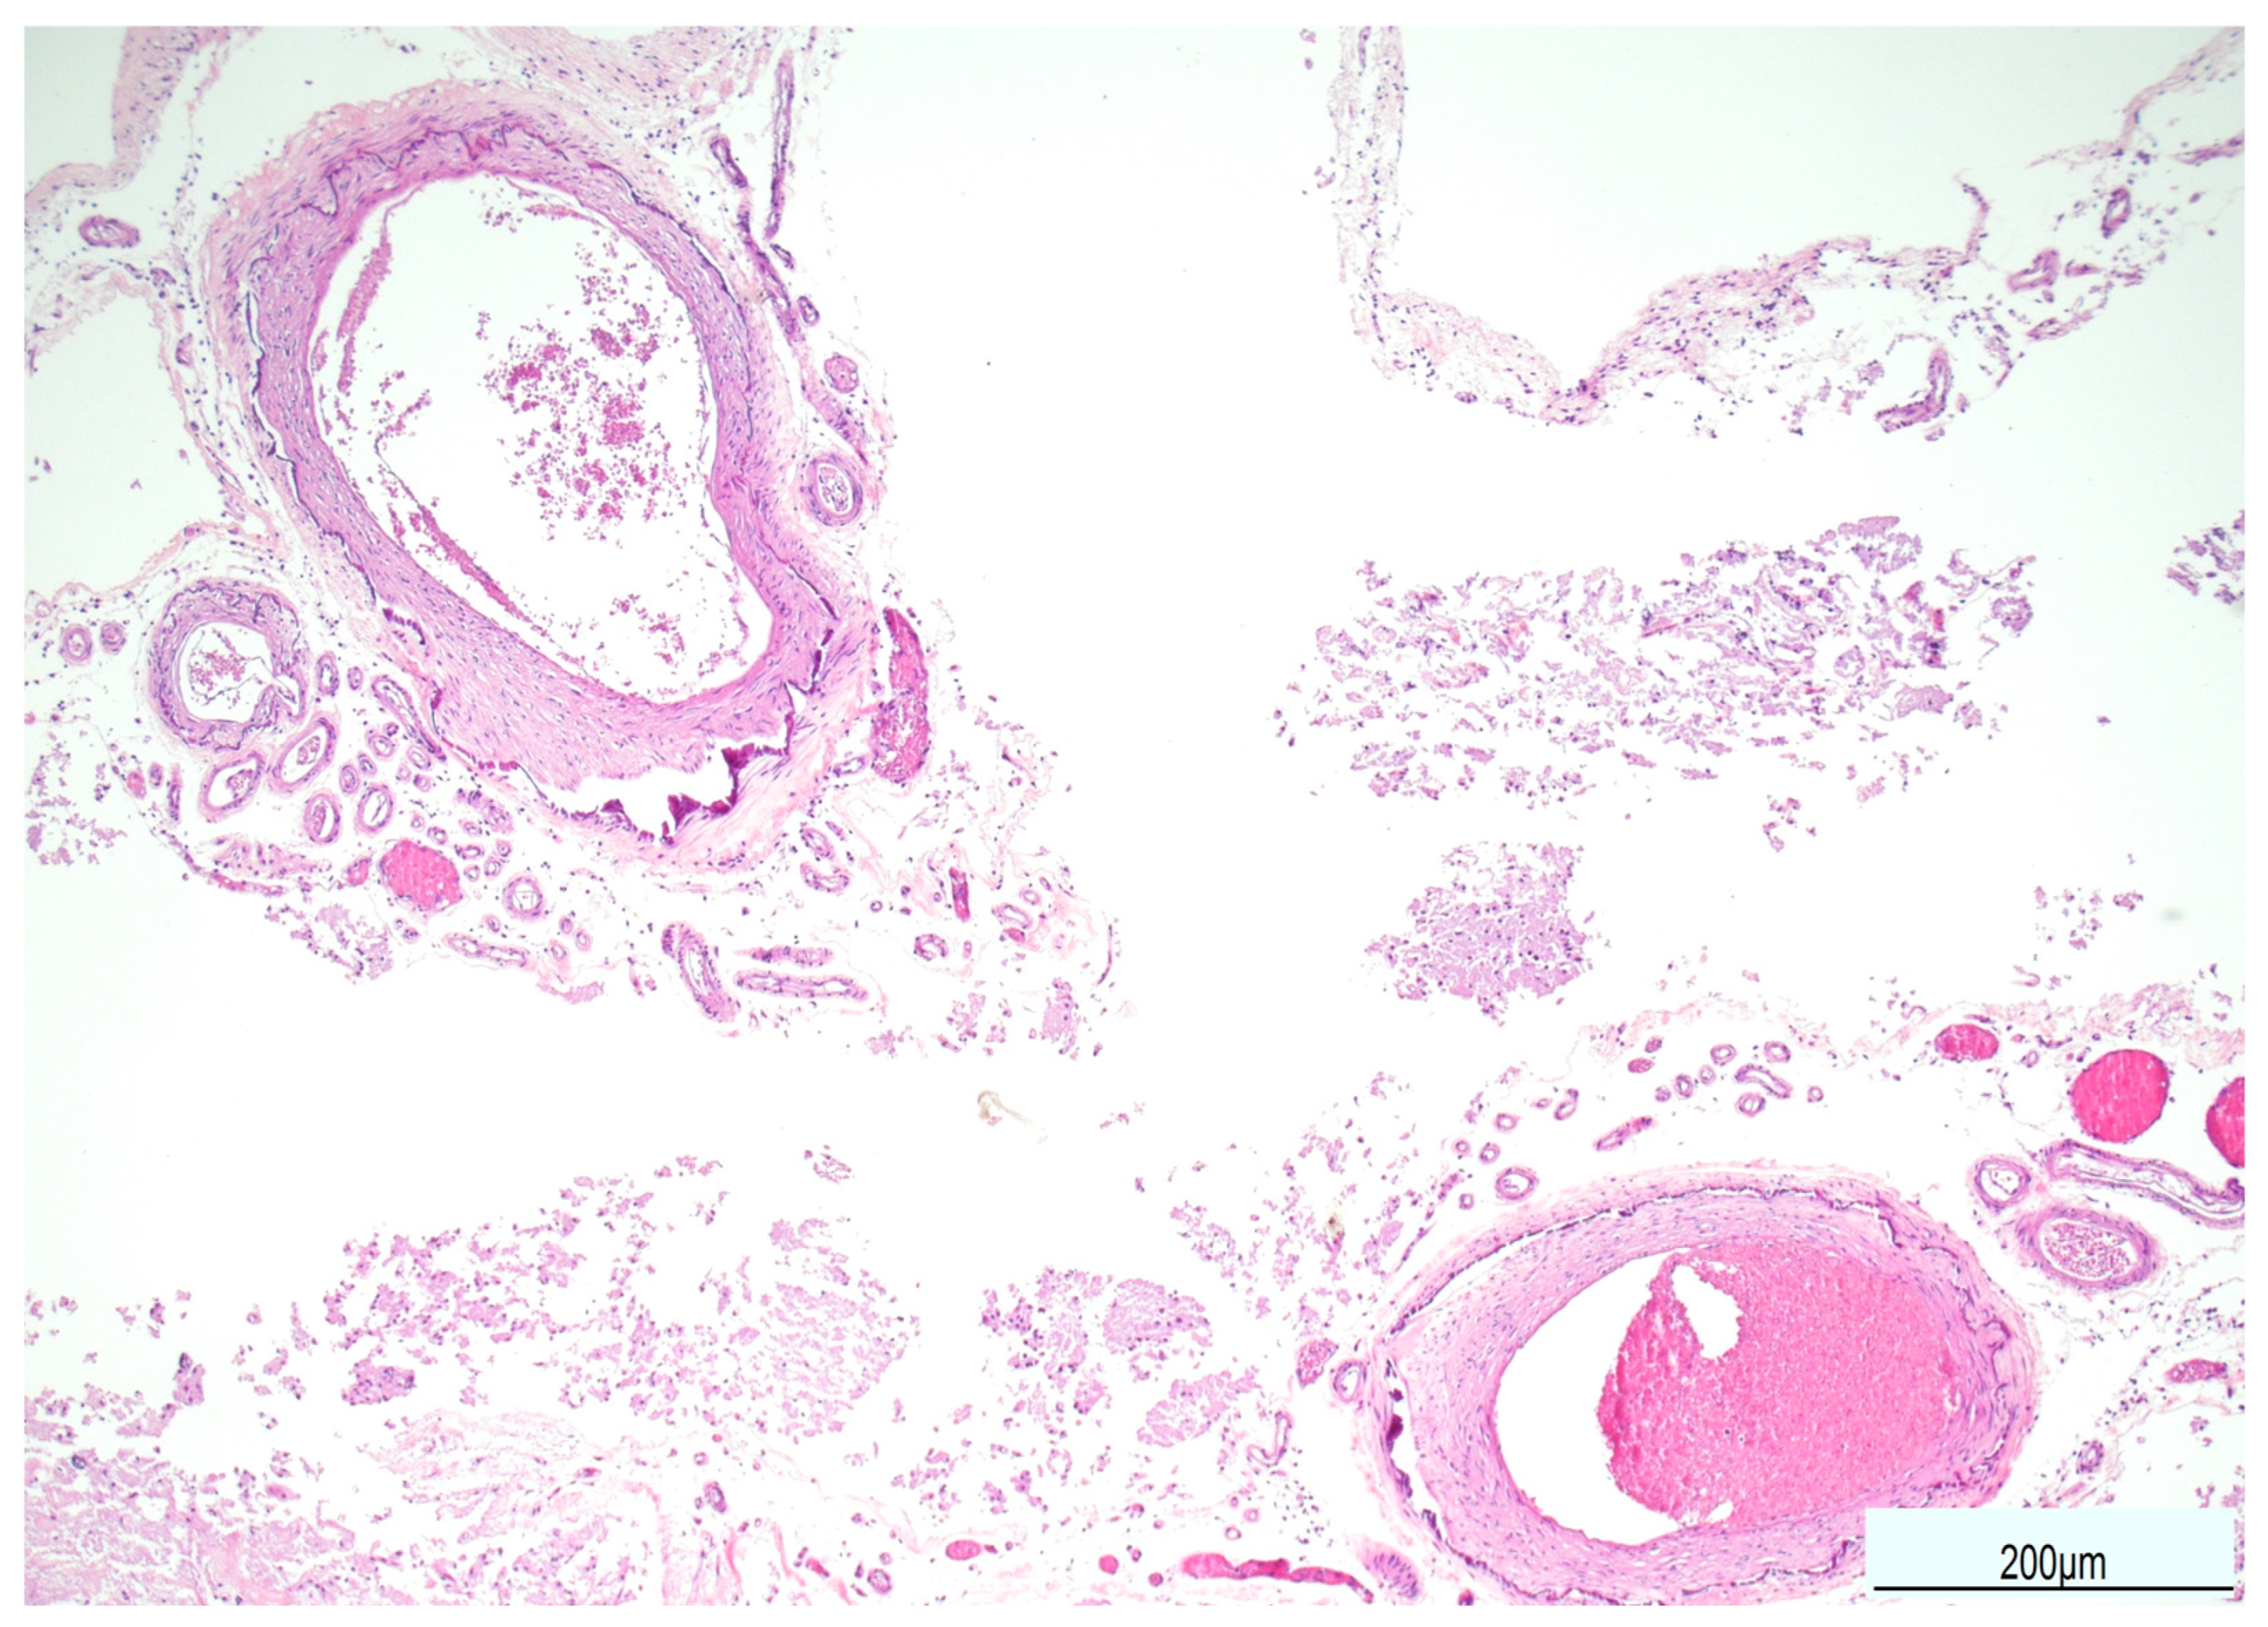

The lungs (right: 350 g, left: 350 g) were reduced in volume, with pinkish-gray coloration in the apico-marginal regions and purplish-red discoloration in the basal areas. The bronchial tree was patent and lined with mucus. The vascular tree was patent and contained fluid blood. On sectioning, the pulmonary parenchyma appeared congested and exuded abundant edema fluid. Considering the radiological diagnosis of pneumonia, microbiological cultures were not carried out. Multiple areas of dark, friable parenchymal consolidation were identified in both lungs and sampled for histological analysis.

The brain was completely removed and fixed in formalin for one month prior to examination. Brain pathology showed marked congestion of meningeal vessels, especially on the left side. The right cerebral hemisphere presented widespread cortical-subcortical malacic areas in the frontal, parietal, temporal, and insular regions. The left hemisphere exhibited frontoparietal cortical-subcortical malacic lesions. There was diffuse dilation of the entire ventricular system (Figure 1, Figure 2 and Figure 3).

Figure 1. Brain gross examination: both cerebral hemispheres showed meningeal congestion, particularly severe on the left ((A,B), top figure). The right hemisphere presented cystic leukomalacia on the frontal, parietal, temporal, and insular regions ((A,B), bottom figure).

Figure 2. Coronal sections of the left hemisphere: the cortex was diffusely atrophic with shrinkage of the white matter and the ventricular system was overall enlarged.

Figure 3. Coronal sections of the right hemisphere: the tissue was extremely friable. However cortical and subcortical cystic malacia was evident in the frontal, parietal, temporal, and insular regions (from top to bottom).